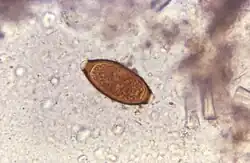

Helminthic therapy

In an experimental idea called helminthic therapy, moderate hookworm infections have been demonstrated to have beneficial effects on hosts who have diseases linked to overactive immune systems. This may be explained by the hygiene hypothesis.[36] Hookworm therapy is currently in the trial stage at the University of Nottingham. Due to the unconventional nature of this therapy, it is not widely used.